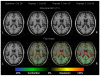

Posterior cortical atrophy (PCA) is a neurodegenerative syndrome that is characterised by progressive decline in visuospatial, visuoperceptual, literacy, and praxic skills. The progressive neurodegeneration affecting parietal, occipital, and occipitotemporal cortices that underlies PCA is attributable to Alzheimer's disease in most patients. However, alternative underlying causes, including dementia with Lewy bodies, corticobasal degeneration, and prion disease, have also been identified, and not all patients with PCA have atrophy on clinical imaging. This heterogeneity has led to inconsistencies in diagnosis and terminology and difficulties in comparing studies from different centres, and has restricted the generalisability of findings from clinical trials and investigations of factors that drive phenotypic variability. Important challenges remain, including the identification of factors associated not only with the selective vulnerability of posterior cortical regions but also with the young age of onset of PCA. Greater awareness of the syndrome and agreement over the correspondence between syndrome-level and disease-level classifications are needed to improve diagnostic accuracy, clinical management, and the design of research studies.